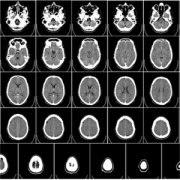

脑膜瘤

法国Froelich教授:醋酸环丙孕酮(CA)停用后,较大脑膜瘤减小且视力恢复

脑膜瘤 和女性性激素之间的关系已得到明确证明,但其潜在机制仍不清楚。孕激素受体在约三分之二的脑膜瘤中强烈表达,但对其在肿瘤发生中的确切作用知之甚少。以往的研究中曾报...